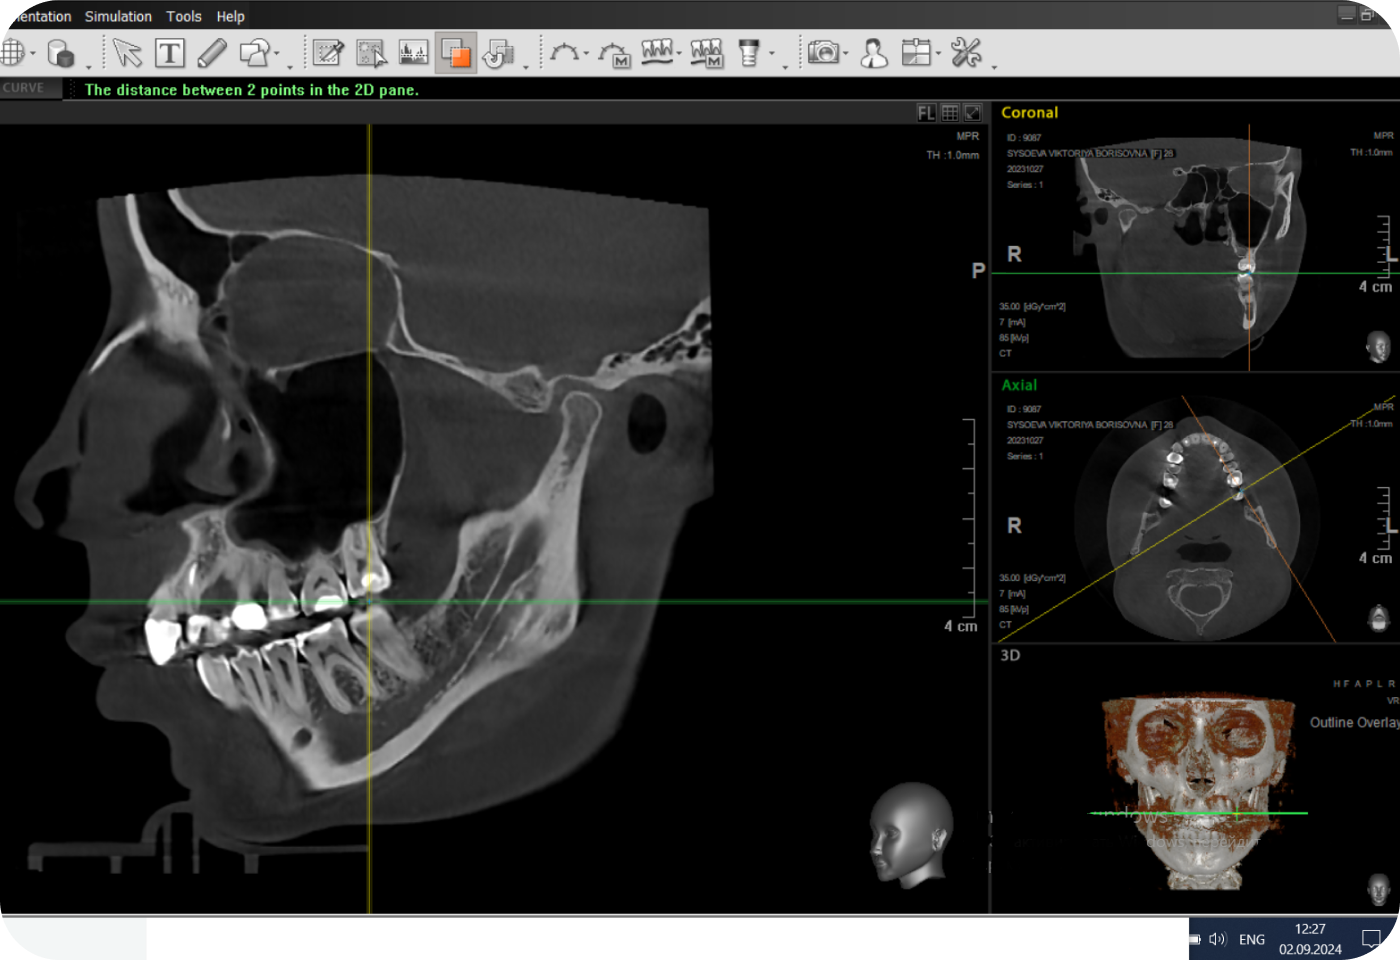

Перед началом лечения я провожу часовую первичную консультацию. Для этой встречи вам необходимо сделать «МРТ ВНЧС» и «КЛКТ двух челюстей с захватом ВНЧС в привычном прикусе».

Во время консультации мы смотрим и анализируем ваши исследования. Я подробно объясняю строение ВНЧС, показываю все причинные факторы вашей проблемы, отвечаю на все вопросы «Почему?»